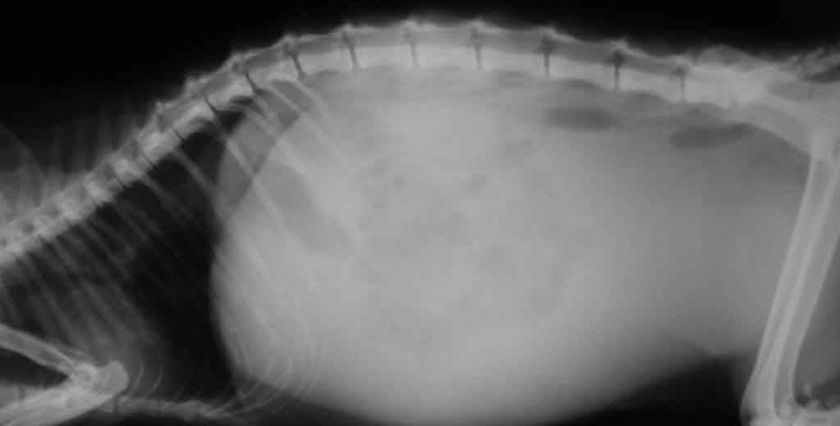

- Augmentation du volume abdominal : l’abdomen peut être gonflé et tendu, indiquant la présence de liquide ou d’air dans la cavité abdominale.

- Examen par échographie. Utilisé pour détecter les changements au niveau des organes abdominaux et identifier la présence de liquide libre dans la cavité abdominale.

- Radiographie. Cet examen permet d'évaluer l'état des organes abdominaux et de détecter les signes d'infiltration.